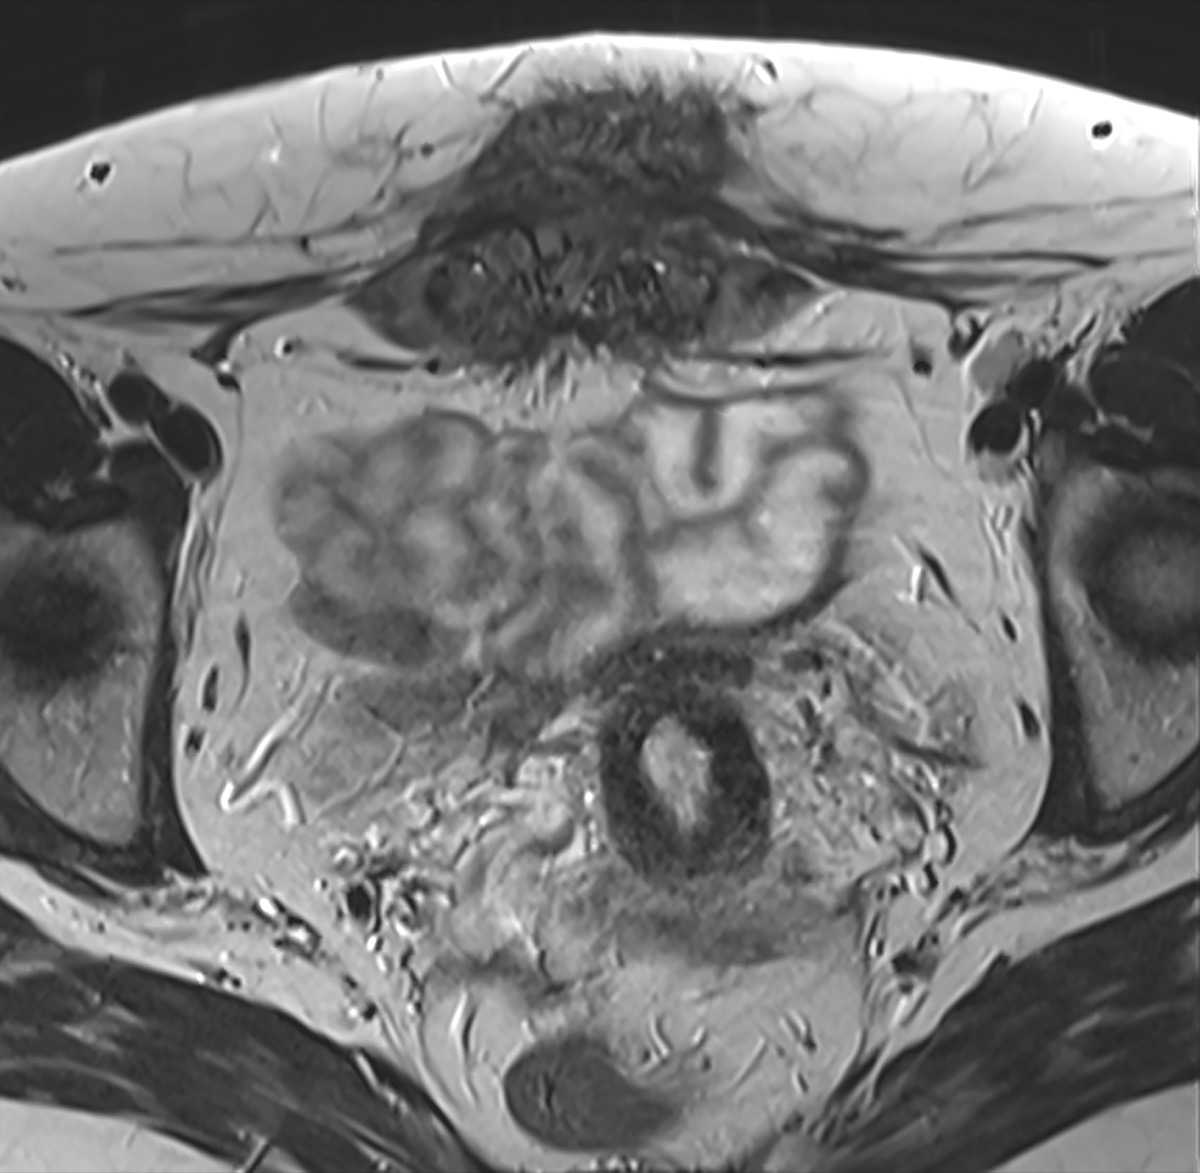

Advancing care through clinical trials

We are spearheading all phases and types of clinical trials, including several sponsored by the NIH, translating novel scientific discoveries into new diagnostics and treatments to help improve clinical outcomes. By enrolling in a clinical trial, you can help our scientists develop new treatments, diagnostic tools and other strategies to prevent, diagnose and treat maternal, fetal, obstetric, gynecologic and women’s health conditions. Through our clinical trials, you may also be able to access emerging technologies and innovative treatments that may otherwise not be available to the general public.

Highlights from our current active clinical trials include: